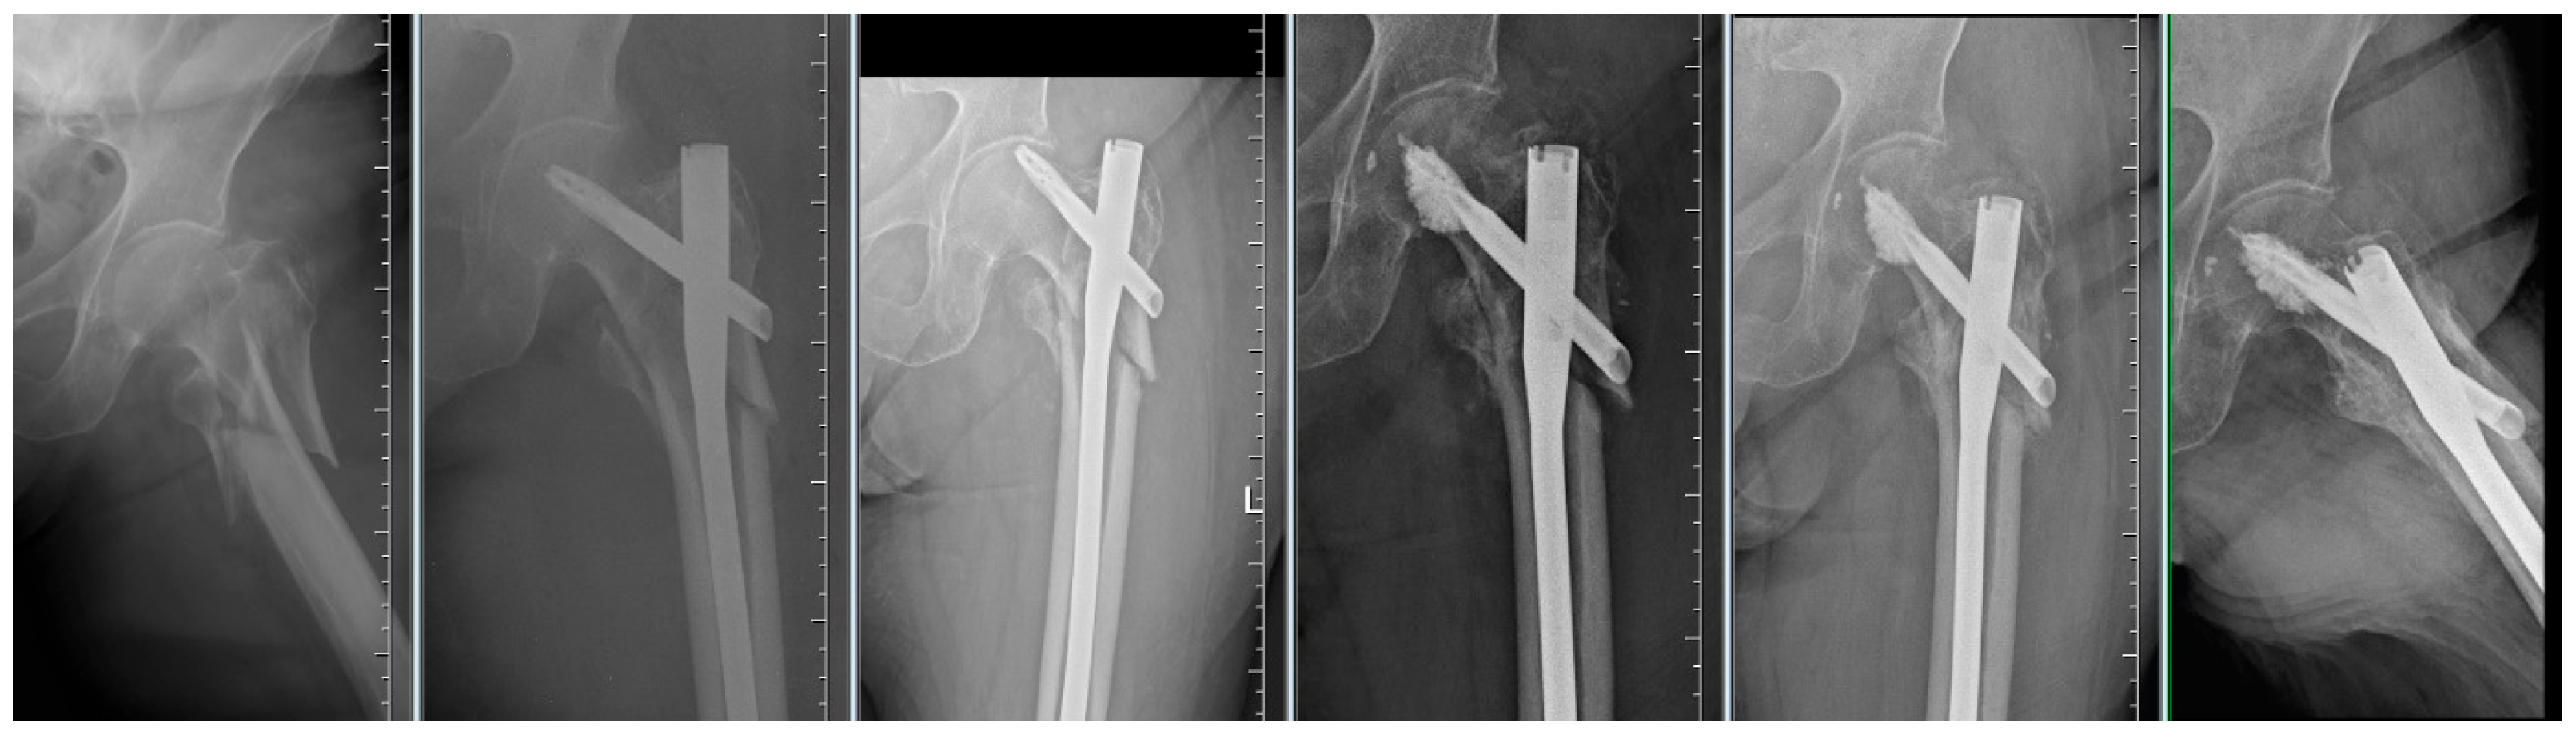

Figure 4.

Failure of osteosynthesis of a comminuted trochanteric fracture treated with TFNA. Reosteosynthesis was performed with cement augmentation of a new blade in the central–inferior position; image shows healed fracture.

By evaluating the X-ray parameters, eight patients in the cohort in whom postoperative varus deformities of the femoral neck were greater than 10° were founded. Four patients did not have cement augmentation and four had cement augmentation of the nail. In three cases, the blade cut-out and, thus, failure of osteosynthesis was identified. In two women and one man with blade cut-out, a TFN-A implant without cement augmentation was implanted (Figure 3, Figure 4 and Figure 5). In these three cases, the medial cortical line and anterior cortical line were repositioned within 3 mm of dislocation at the anatomical interface. The blade cut-out in the group with cement augmentation was not observed.